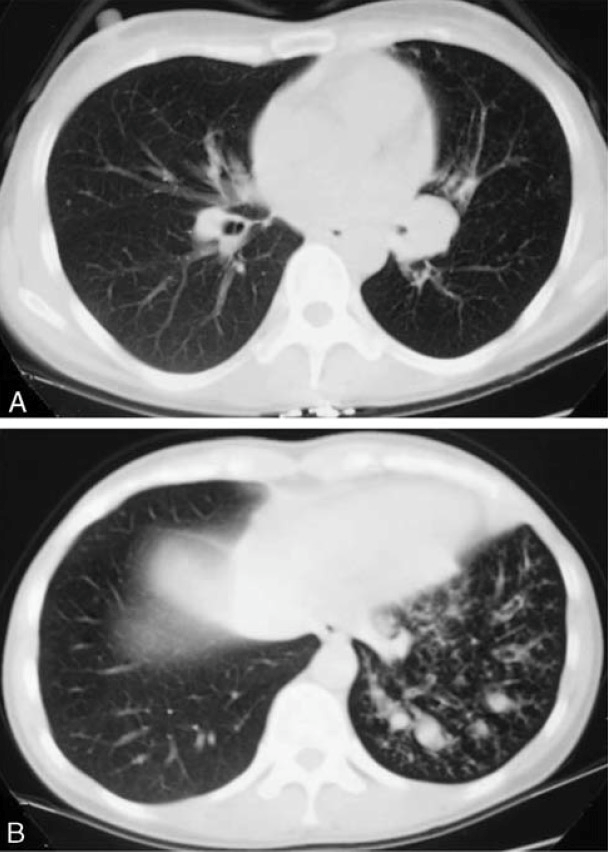

慢性肺血栓栓塞是肺动脉血流减少的一种常见原因。以下是一例50岁非吸烟者的胸部CT图像,患者既往有双侧大面积急性肺栓塞病史,3年后转为慢性肺栓塞。薄层CT吸气相可见右肺叶各支气管分支有圆柱状扩张伴微小动脉影,呈现与印戒征相似的影像学表现(箭头),舌部存在马赛克征[8]。

50岁慢性肺血栓栓塞患者的胸部CT:印戒征样影像学表现[8]